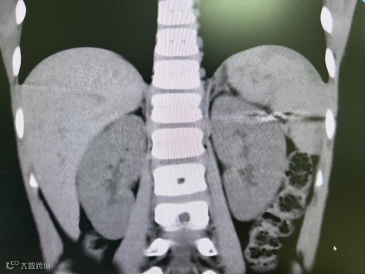

一场快乐的户外游玩,因一次攀高不慎戛然而止。10月13日下午,8岁的小金(化名)在攀爬高处时不慎摔下,因为没有明显外伤,所以当时家长只是带回家观察,并未做特殊处理,直到晚上小金说左侧肋部疼痛越来越剧烈,家长这才匆忙将他送来北海市第二人民医院急诊就医。经验丰富的急诊医生觉察到,小金大概率有内伤!CT检查结果揪紧了所有人的心:脾破裂并出血。

经过后续的精心治疗与观察,患儿目前已恢复良好得以出院。他保住的不仅是一个器官,更是一个无忧无虑、健康完整的童年。

出院后10天复查情况良好